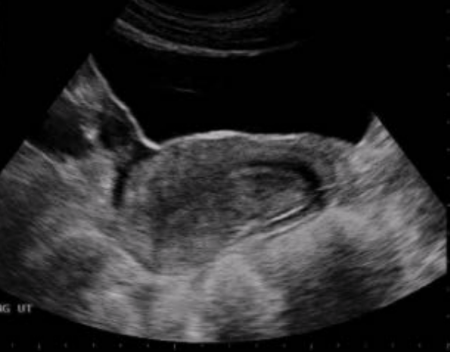

What position is this uterus in?

a. Anteverted

b. Retroverted

c. Anteflexed

d. Retroflexed

Retroverted